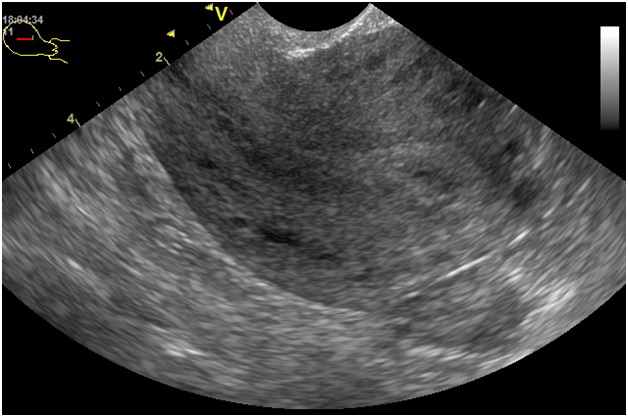

Миома на ультразвуковом исследовании

Миома

Гиперэхогенность в матке, наблюдаемая при миоме, может свидетельствовать о прогрессировании заболевания или наличии кальцинатов. Эти образования выглядят как своеобразные включения.

Наиболее распространено наличие множественных миом, которые оказывают негативное воздействие на состояние матки, нарушая ее анатомическую структуру и изменяя положение полости.